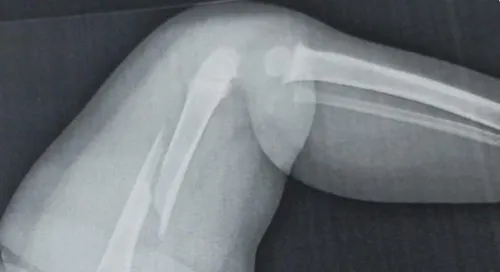

Autor Além da fratura na perna, o menino apresentava lesões antigas - Foto: Reprodução

A Polícia Civil de Paiçandu investiga uma possível agressão contra um bebê de um ano e cinco meses, internado com o fêmur fraturado em Maringá, no noroeste do Paraná. Durante o atendimento médico, os profissionais identificaram, além da lesão recente, uma fratura antiga no braço da criança, o que reforçou as suspeitas de maus-tratos.